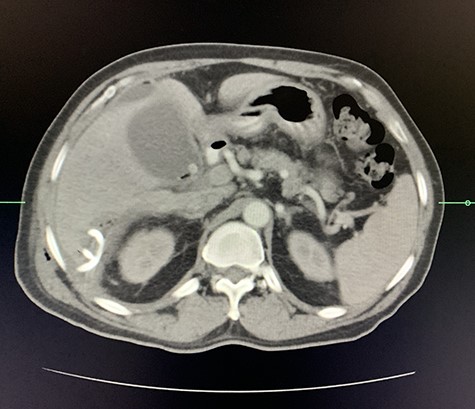

A computed tomography (CT) scan of the abdomen revealed an enlarged, thickened gallbladder with multiple stones, communicating with an intrahepatic collection in segment 4 measuring 116 × 80 mm, with an associated air fluid level and air locules (Fig. 1). There was an apparent fistulous tract to the hepatic flexure of the colon, another large collection in segment 6 (97 × 96 mm) as well as other smaller collections (Figs 2 and 3).

Coronal view of oral and intravenous contrasted CT scan of the abdomen demonstrating features of cholecystitis with fistulous communication with the hepatic flexure of the colon with associated pneumobilia.